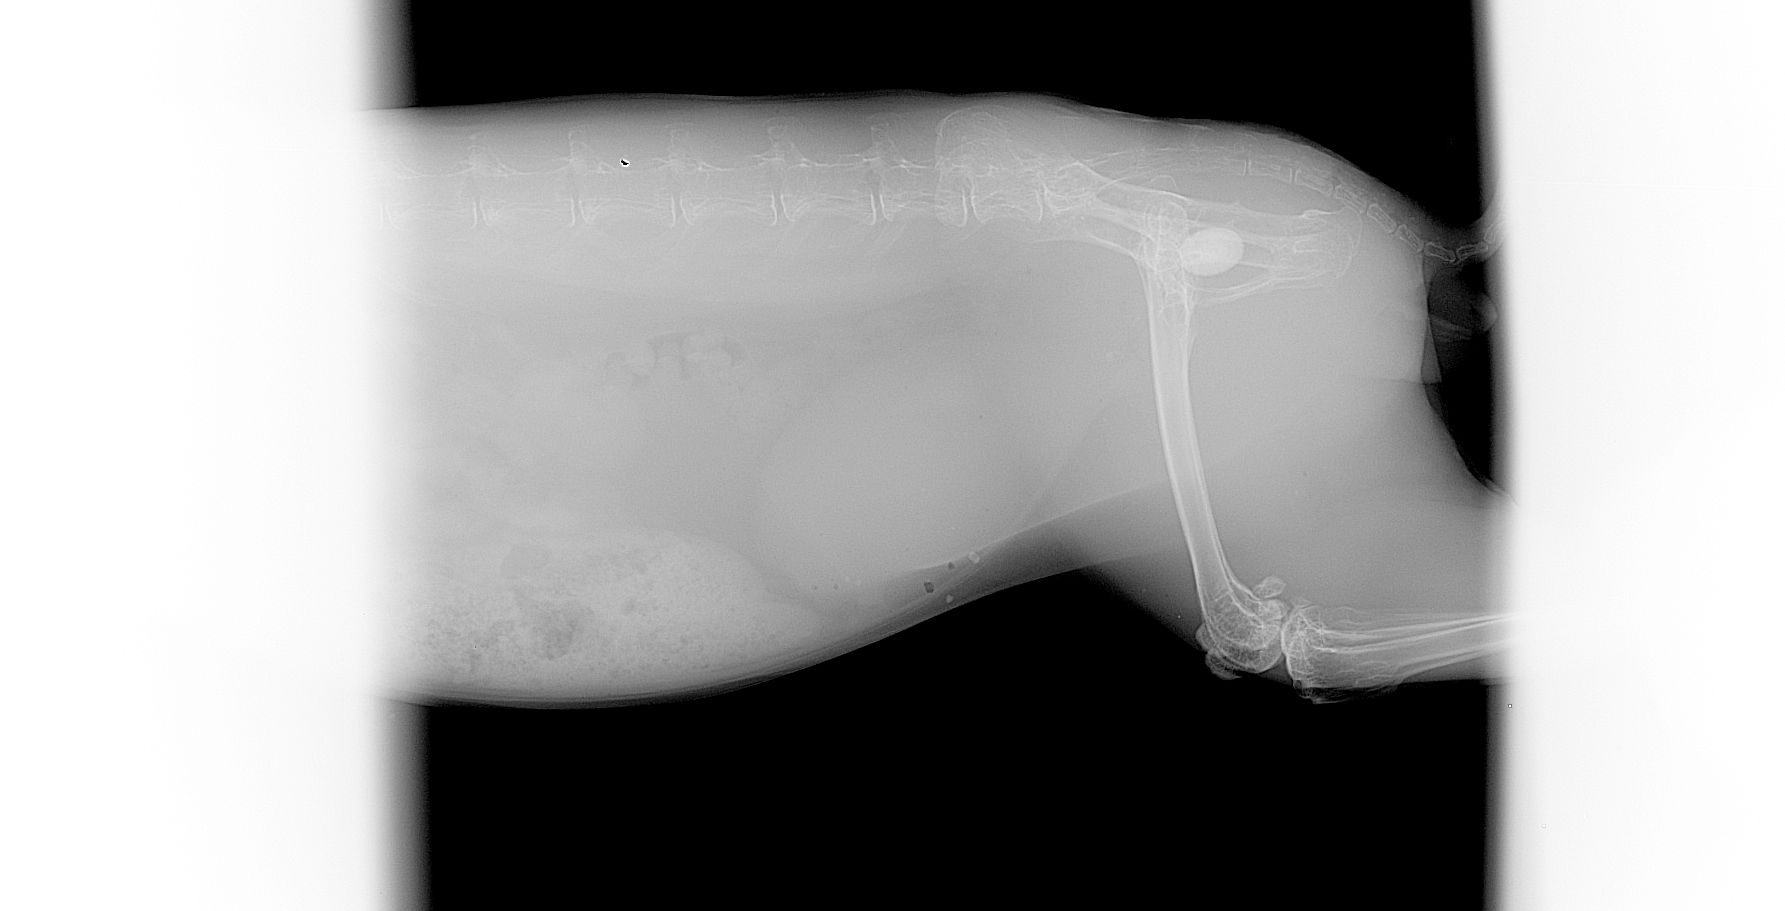

Le diagnostic se fait par radiographie mais une échographie et une prise de sang sont recommandés pour exclure la présence d'autres calculs au niveau des uretères et des reins et aussi pour vérifier l'absence d'insuffisance rénale. Le traitement est quasiment toujours chirurgical, certains cas particulier peuvent être traité par endoscopie ou par traitement médical.

Une infection par E.cuniculi peut éventuellement prédisposer à la formation de calculs. Les calculs rénaux se voient généralement à la radiographie mais certains calculs ne peuvent être visualisés que par échographie.

Suivant l'extension des calculs et la gravité de l'insuffisance rénale, le pronostic est réservé. Il peut être recommandé de faire une néphrotomie pour retirer les calculs mais les récidives sont fréquentes. Un ajustement de l'alimentation pour limiter les apports en calcium est impératif.